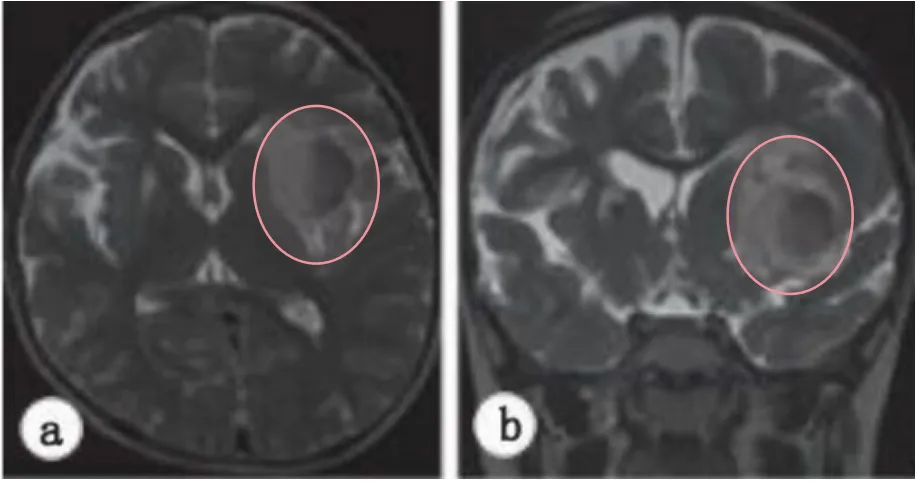

一次常规的随访,让桃子一家人重新开始胆战心惊。MRI发现左侧岛叶有一个小病变(图3a&b)。复查脑MRA又显示在左侧MCA远端,有一个动脉瘤样的圆形病变(图3c)。然而,进一步的DSA检查排除了一个动脉瘤(图3d)。

尽管排除了脑内血肿或海绵状血管瘤等其他可能,但是由于桃子目前暂无症状,因此建议选择保守治疗,同时减少阿司匹林剂量(2.5mg/5kg/天)。

图3:轴向(a)和冠状(b)T2加权磁共振图像显示,左侧岛叶皮质有一个小的圆形混合强度质量(箭头)。(c)体积渲染磁共振血管造影显示,在大脑中动脉的左远端(箭头)发现一个浆果状病变,怀疑大动脉瘤。(d)左侧颈内动脉造影术未发现动脉瘤等异常表现。